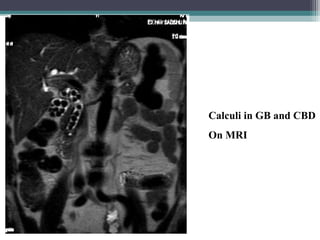

Calculi in GB and CBD

On MRI

Calculi in GBand CBD On MRI